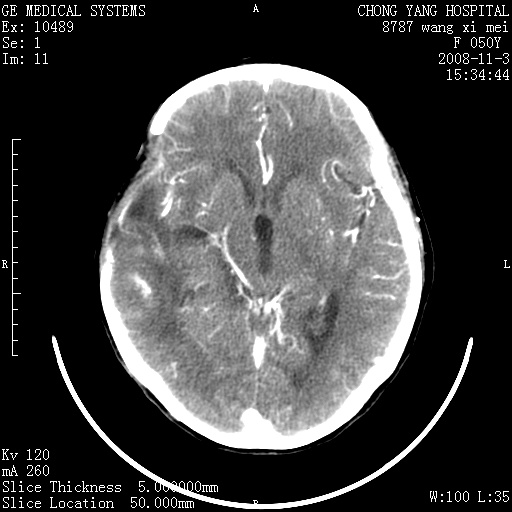

右侧颞顶部可见低密度实变影,内见不规则钙化灶,边界不清,占位效应明显,侧脑室后角受压移位,符合胶质瘤术后复发改变。

右颞骨局限性缺如,局部脑组织无外隆。右颞叶可见片状脑脊液样低密度影,边缘较清,右侧侧脑室三角区可见一块状等密度影,且伴有强化,余未见明显异常改变。

考虑:右大脑术后改变伴肿瘤复发。

手术后局部片状低密度改变(软化灶),其后方颞叶似等密度病灶,界限不清,内见钙化,有轻度占位效应,但增强后强化之血管走行如常。应不考虑:复发!

考虑右侧颞顶叶胶质瘤术后复发。

应考虑肿瘤复发,右颞顶叶已出现轻度强化肿块.必要时可与原片比较以下.

右侧颞顶部混杂密度影,内有钙化,有占位效应。应该是复发灶。结合术后片更好。